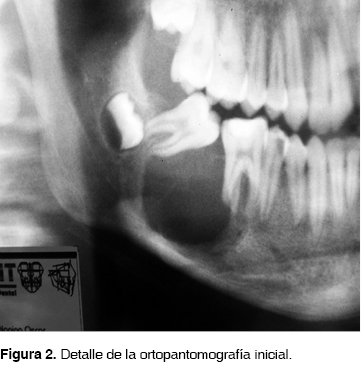

En julio del 2004 se presentó a la Consulta Externa del Hospital Juárez de México un adolescente del sexo masculino de 14 años de edad, con aumento de volumen mandibular del lado derecho, aparentemente de 7 meses de evolución, presentando ligera sintomatología dolorosa a la presión y sin antecedentes previos de relevancia para su padecimiento. La lesión se extendía del segundo premolar a zona del tercer molar derecho, produciendo expansión vestibular, con desplazamiento y movilidad del primero y segundo molar ipsilateral (Figura 1). La radiografía panorámica mostró una lesión radiolúcida unilocular que abarcaba primer y segundo molar derechos con íntima relación al tercer molar, bordes bien delimitados, de dimensiones aproximadas de 30 x 20 mm, produciendo desplazamiento de los órganos dentales involucrados (Figura 2). La TAC simple mostró una lesión que producía adelgazamiento y expansión cortical vestibular y lingual conservando el borde mandibular (Figura 3).